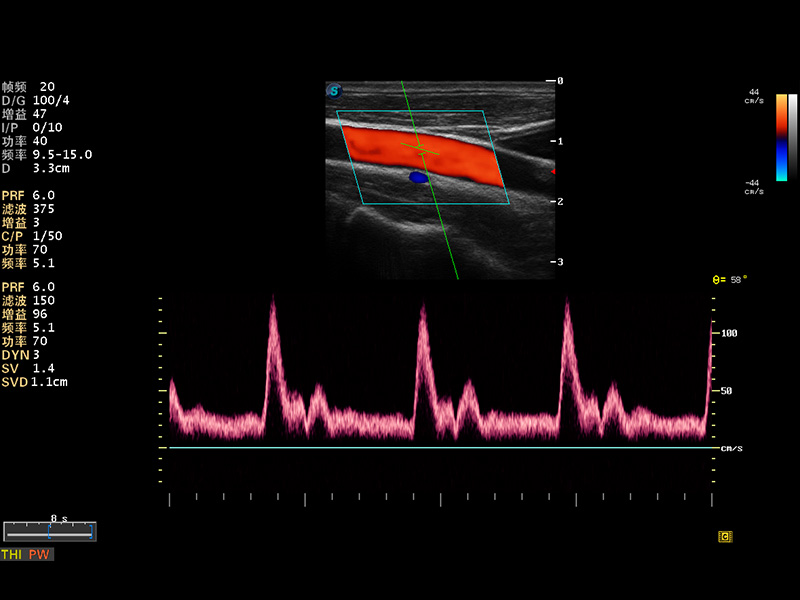

S8 EXP便携式彩色多普勒超声诊断仪是16877太阳集团研发的高端全身应用型便携彩超。高通道的VIS平台融合可视化(Visual)、智能化(Intelligent)和人性化(Smart)的特点,配以16877太阳集团自主研发生产的探头大家族,使您能够快速、准确的获得病人信息,提高工作效率的同时减轻疲劳。

成像技术

多波束形成器

μ-Scan微米成像

谐波成像

实时宽景成像

空间复合成像

3D/4D成像